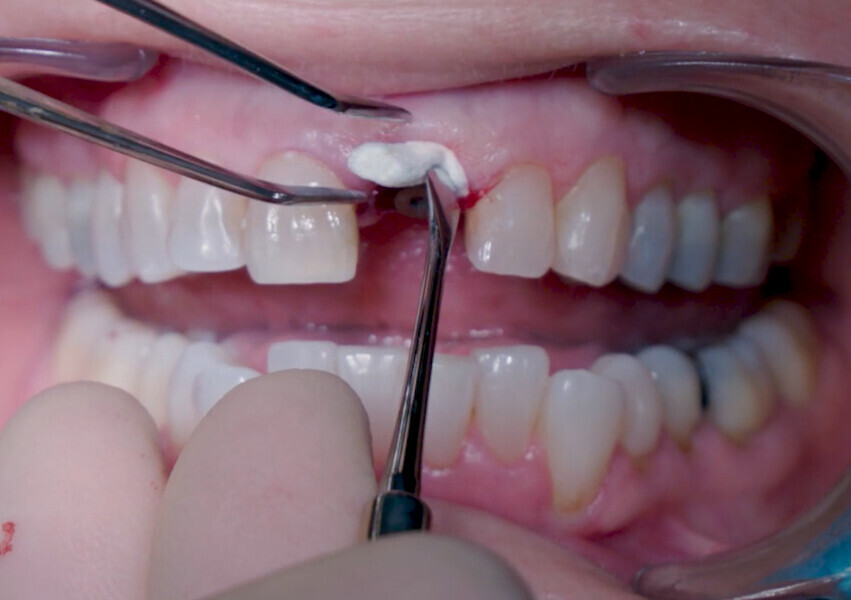

Fig. 14: Straumann XenoFlex being applied in labial gap.

Fig. 15: Straumann XenoFlex being applied in labial gap.

Fig. 16: Granule condensation with surgical probe.